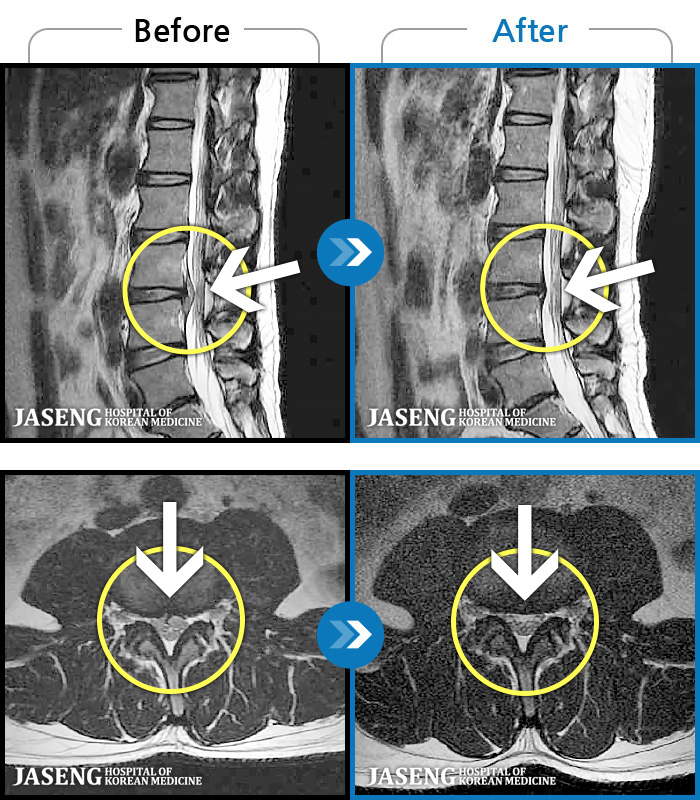

[Կñ:23.08.01~23.11.18]

[_㸮ũ] 㸮 ٸ ؼ ɰų

No.116

ȸ 663

2023.12.08